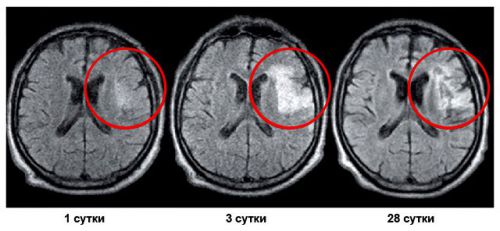

Геморрагический инсульт

Возникает из-за, наоборот, усиленного притока крови к мозгу, которая из-за повышенного напора попросту разрывает артерию. Чаще всего геморрагический инсульт случается во время гипертонического криза, когда резко повышается кровяное давление. Поэтому очень важно контролировать свое артериальное давление.